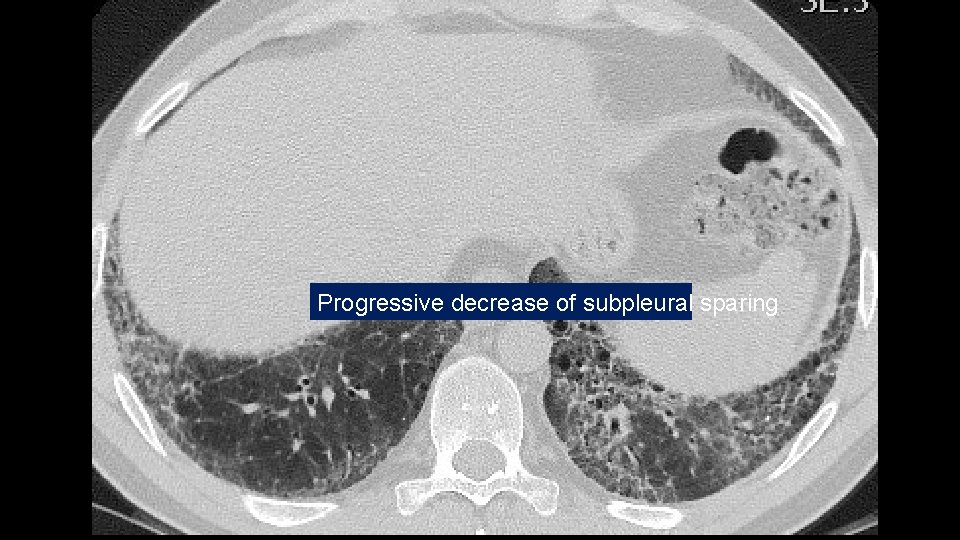

Progressive decrease of subpleural sparing